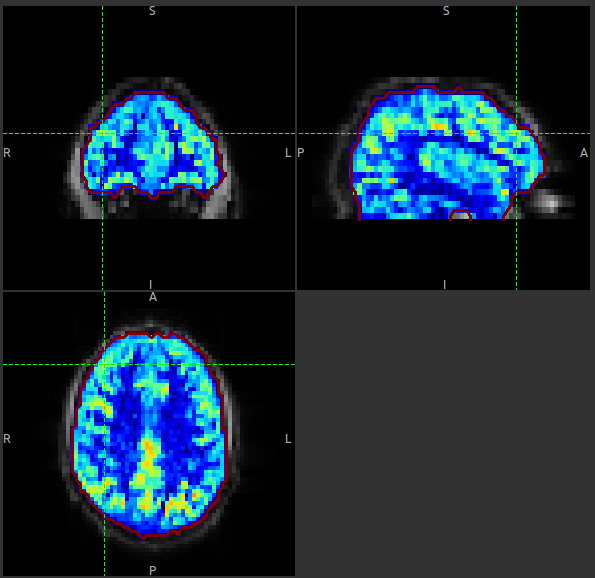

Arterial Spin Labelling MRI Perfusion

Arterial Spin Labelling (ASL) is an MRI method for imaging the delivery of blood to body tissues, and is most widely used in the brain. By manipulating the the magnetization of blood water before entering the tissue the blood is labelled without the need to introduce a contrast agent.

Using ASL it is not only possible to generate perfusion-weighted images, but also make spatially resolved measurements of perfusion in absolute units (e.g., ml blood/100g tissue/min).